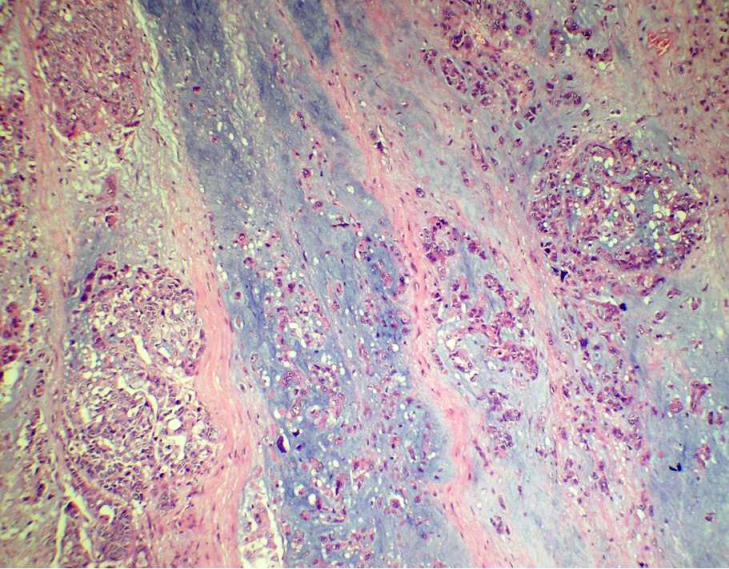

Figure 4: Photomicrograph showing invasive ductal carcinoma with an abrupt transition to chondromyxoid matrix without an intervening spindle cell component (H&E 200X)

A 55-year-old female presented with a mass in the medial aspect of the right breast. Clinically, a single 4×3 cm, non tender, firm, and mobile lump was palpable in the right breast in the lower inner quadrant without nipple retraction or skin adhesion. This was confirmed mammographically. The left breast and axillary lymph nodes were uninvolved. Hematological, biochemical, and metastatic workup were normal. Incisional biopsy of the lump was diagnosed as IDC with chondroid areas and the patient was staged as T2N0M0 on TNM classification. Subsequently, modified radical mastectomy with axillary node dissection was performed. Grossly, cut surface revealed a fibrous, grey-white, partly encapsulated 3.5×3 cm tumor with mucoid and glistening areas (Figure 1 [Fig. 1]). Microscopically, the tumor had two distinct patterns; high grade IDC (Figure 2 [Fig. 2]) and tumor cells scattered singly, in groups and cords within a chondromyxoid matrix. These were medium- to large-sized, chondrocyte-like oval-shaped with atypical nuclei and eosinophilic cytoplasm. Mucoid to overtly cartilaginous areas were identified in the matrix (Figure 3 [Fig. 3]). The chondromyxoid matrix was multifocal, of high grade with abrupt transition between IDC component and metaplastic areas (Figure 4 [Fig. 4]). No lymphovascular invasion was identified, surgical margins and lymph nodes were uninvolved by carcinoma. Due to the presence of IDC component and chondroid metaplastic areas, the diagnosis of matrix-producing metaplastic carcinoma of breast was rendered. This was further confirmed by immunohistochemical profiling. The tumor was negative for hormone receptors and HER2/neu. IDC cells stained positive for cytokeratin and negative for S100 (Figure 5 [Fig. 5]). MPC areas revealed immunoexpression for S100 and were negative for cytokeratin (Figure 6 [Fig. 6]). The patient was given six cycles of chemotherapy and local radiation therapy and is well two years post surgery.